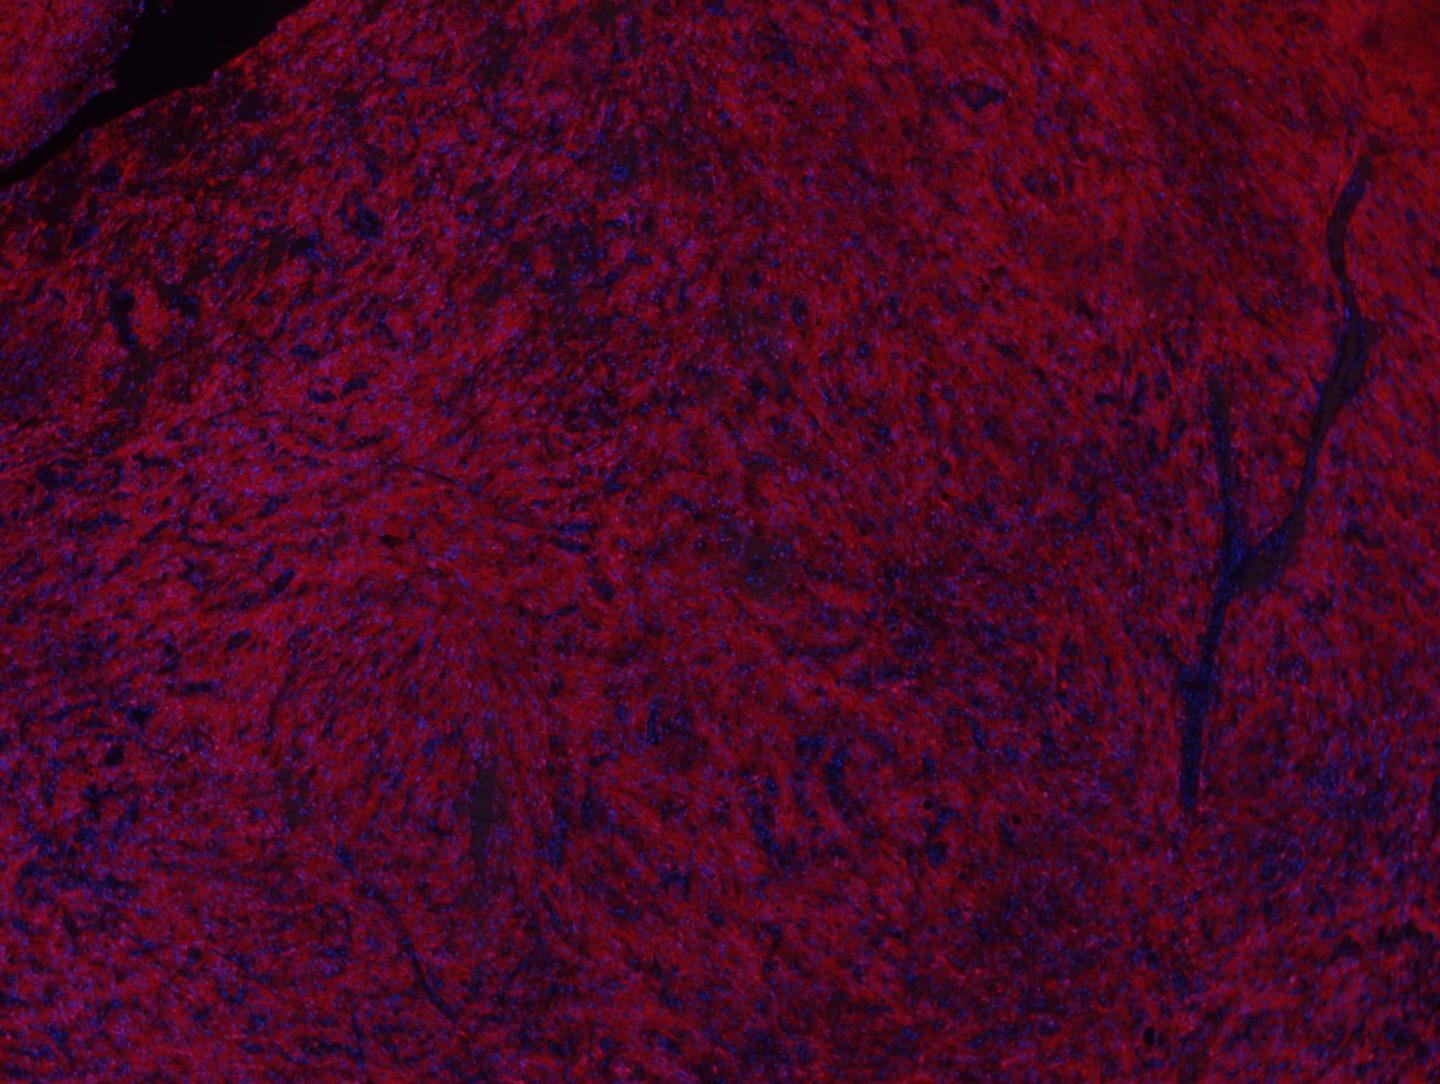

A similar drug might be able to tame some brain cancers, new research from Columbia University Medical Center has shown. A team led by Antonio Iavarone, MD, professor of neurology and of pathology and cell biology, Institute for Cancer Genetics, previously discovered that a fusion of two proteins (present only in cancer cells and different from the two in CML) drives some cases of glioma, a common form of brain cancer.

The team's most recent study, published in Clinical Cancer Research , looked closely at two patients affected by recurrent glioblastoma with the fused proteins, in a first in-human trial of a drug that targets half of the fusion protein. Those patients, the researchers found, responded particularly well to the drug, with clinical improvement and radiological tumor reduction. The responses lasted 115 and 134 days, respectively.

The study also found the fused protein in a significant fraction of the 795 glioma cases they examined, indicating that a smart drug that targets the fused proteins could have a meaningful impact.